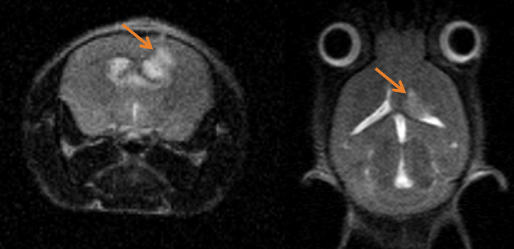

Monitoring tumor growth in the mouse brain, following the orthotopic injection of glioblastoma cells, using T2-weighted images. Image Credit: Scintica Instrumentation Inc

Multimodal Imaging: Multimodal imaging combines the strength of MRI with other imaging modalities such as PET and CT. PET provides information on the spatial distribution of molecular signal of interest. In this case MRI confirmed that the absence of tracer uptake in the center of the images was due to the presence of a necrotic core, which appears hyperintense on T2-weighted MRI. Image Credit: Scintica Instrumentation Inc

Multimodal imaging combines the strength of MRI with other imaging modalities, such as PET and CT. PET provides information on the spatial distribution of molecular signal of interest. In this case MRI confirmed that the absence of tracer uptake in the center of the images was due to the presence of a necrotic core, which appears hyperintense on T2-weighted MR. Image Credit: Scintica Instrumentation Inc